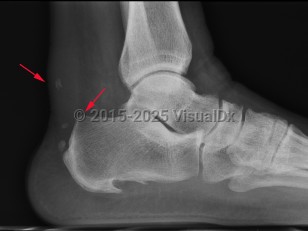

Imaging Studies image of Achilles tendonitis - imageId=7886591. Click to open in gallery.  caption: '<span>Achilles Tendonitis - rupture.  Lateral ankle radiograph demonstrates soft tissue thickening and  multiple, small dystrophic calcifications involving the distal Achilles  tendon compatible with chronic Achilles tendonitis. Note the presence of  a small bony bump along the posterosuperior calcaneus which may be the  early signs of a Haglund deformity.</span>'

Achilles Tendonitis - rupture. Lateral ankle radiograph demonstrates soft tissue thickening and multiple, small dystrophic calcifications involving the distal Achilles tendon compatible with chronic Achilles tendonitis. Note the presence of a small bony bump along the posterosuperior calcaneus which may be the early signs of a Haglund deformity.